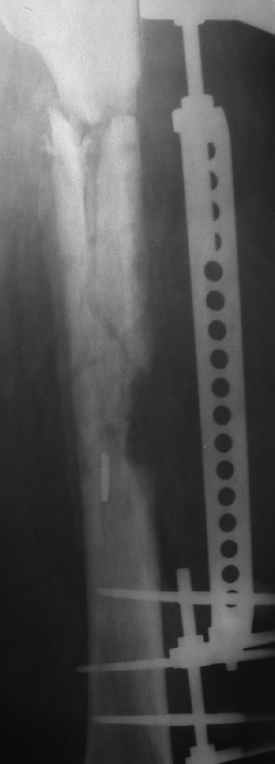

Больной 40лет, поступил 08.06.05г. с закр. оскольчатым переломом бедренной кости в с/3 и в/3 со смещ., 10.06.05г. выполнен остеосинтез LCP

,ч/з 3нед. после операции вскрыта нагноившаяся гематома, промывная система 1нед., через 3-и месяца пластина удалена в связи с инфекцией, секвестрэктомия, ЧКДО. АВФ 8мес.,периодически абсцедирование мягких тканей, санирующие операции, в настоящее время вскрыт абсцесс в с/3 бедра, м/ткани в обл. стержней инфицированы, полость абсцесса сообщается с проксим. и частью дист. стержнейдальнейшая тактика?